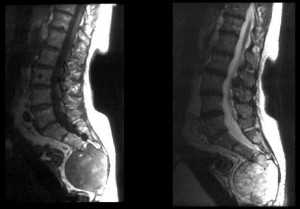

Метастазы в позвонки. Т2-зависимая МРТ.